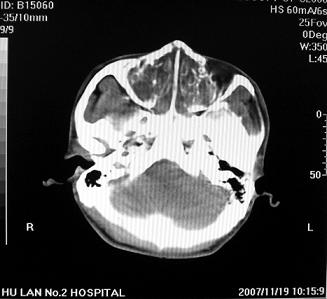

标题: CT10521:男。32岁,副鼻窦ct,请会诊。

男。32岁,鼻塞,流涕一年余。

软组织密度影填满上颌蚪 筛窦及鼻腔,并导致筛骨 上颌窦内侧壁明显骨质破坏。多考虑:内翻性乳头状瘤!

双侧鼻腔内低密度软组织影,骨壁无明显破坏,鼻腔无扩大,双侧上颌窦、筛窦软组织影,窦壁增厚,结合临床考虑鼻息肉合并慢性上颌窦炎。